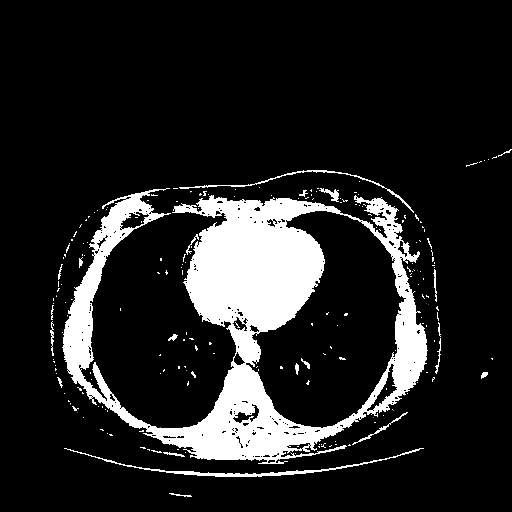

Original VENOUS CT scan

Full window (WL 1023.5, WW 4095 β†’ Low βˆ’1024, High +3071)

Actual HU range: [-1024.0, 3071.0]